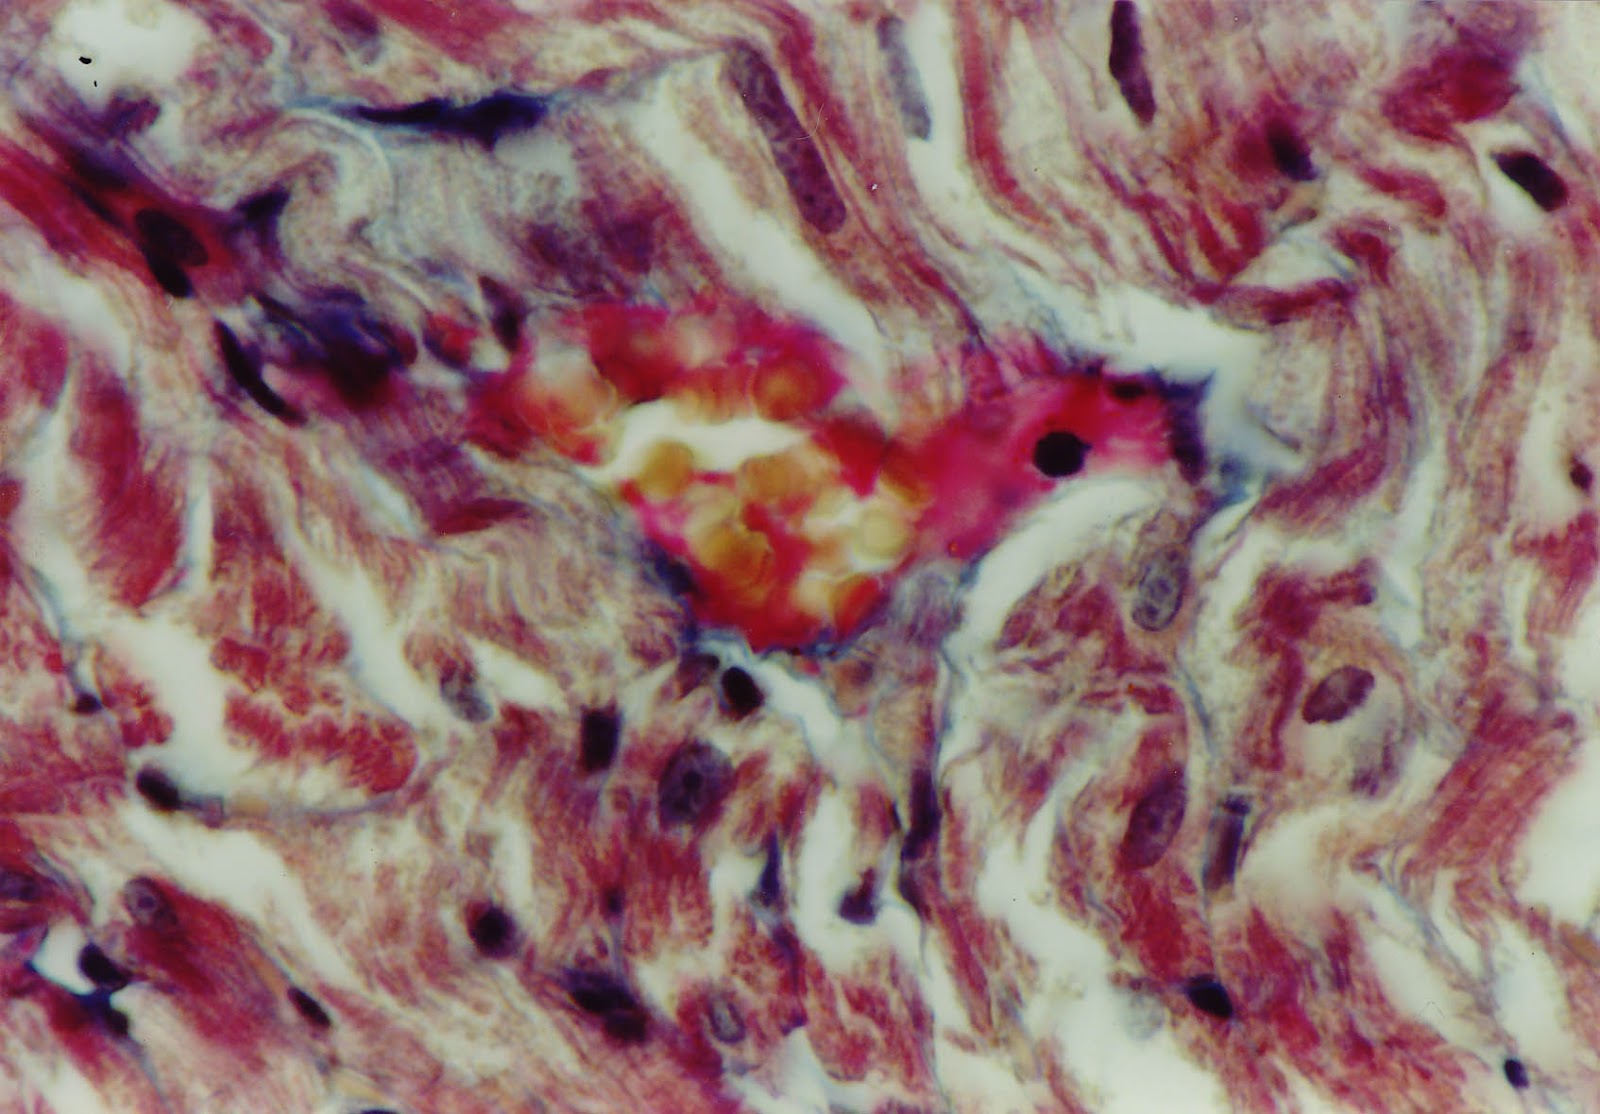

Myocardium. Arteriole and venule blocked by hematic thromb

Degenerative and necrotic areas due to the partial obstruction (+85%)

of arteriole lumen – mixt thrombus.

Partial thrombosis of an arteriole lumen. The adhesion

of the thrombus on the vascular endothelium can be observed.

Intense fixation area of myofibrilla postinfarct

Distrophia and microfocus of miofibrilar necrosis